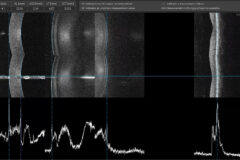

With a unique combination of super-fast scanning at 130,000 scans per second and ultra-high 3 µm resolution, this powerful device takes precision, accuracy, and detection of even the finest lesions to a whole new level.

The system provides 3 µm resolution imaging, enabling detailed visualization of fine ocular structures and improved detection of subtle pathological changes.

The combination of super-fast scanning at 130,000 scans per second and 3 µm High Resolution will provide a powerful tool for optimising precision, accuracy and improving the detection of the smallest lesions in tissue.